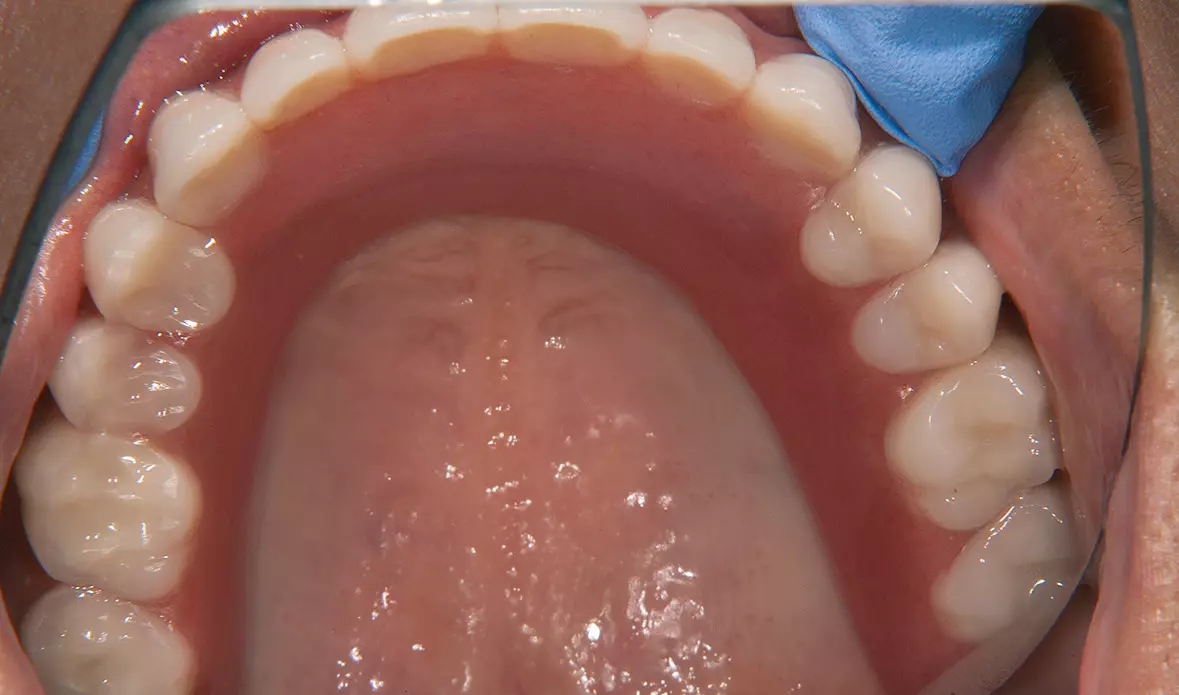

Abb. 4: Oberkiefer vor Implantatinsertion. Dr. Michael Leistner

Abb. 4: Oberkiefer vor Implantatinsertion.